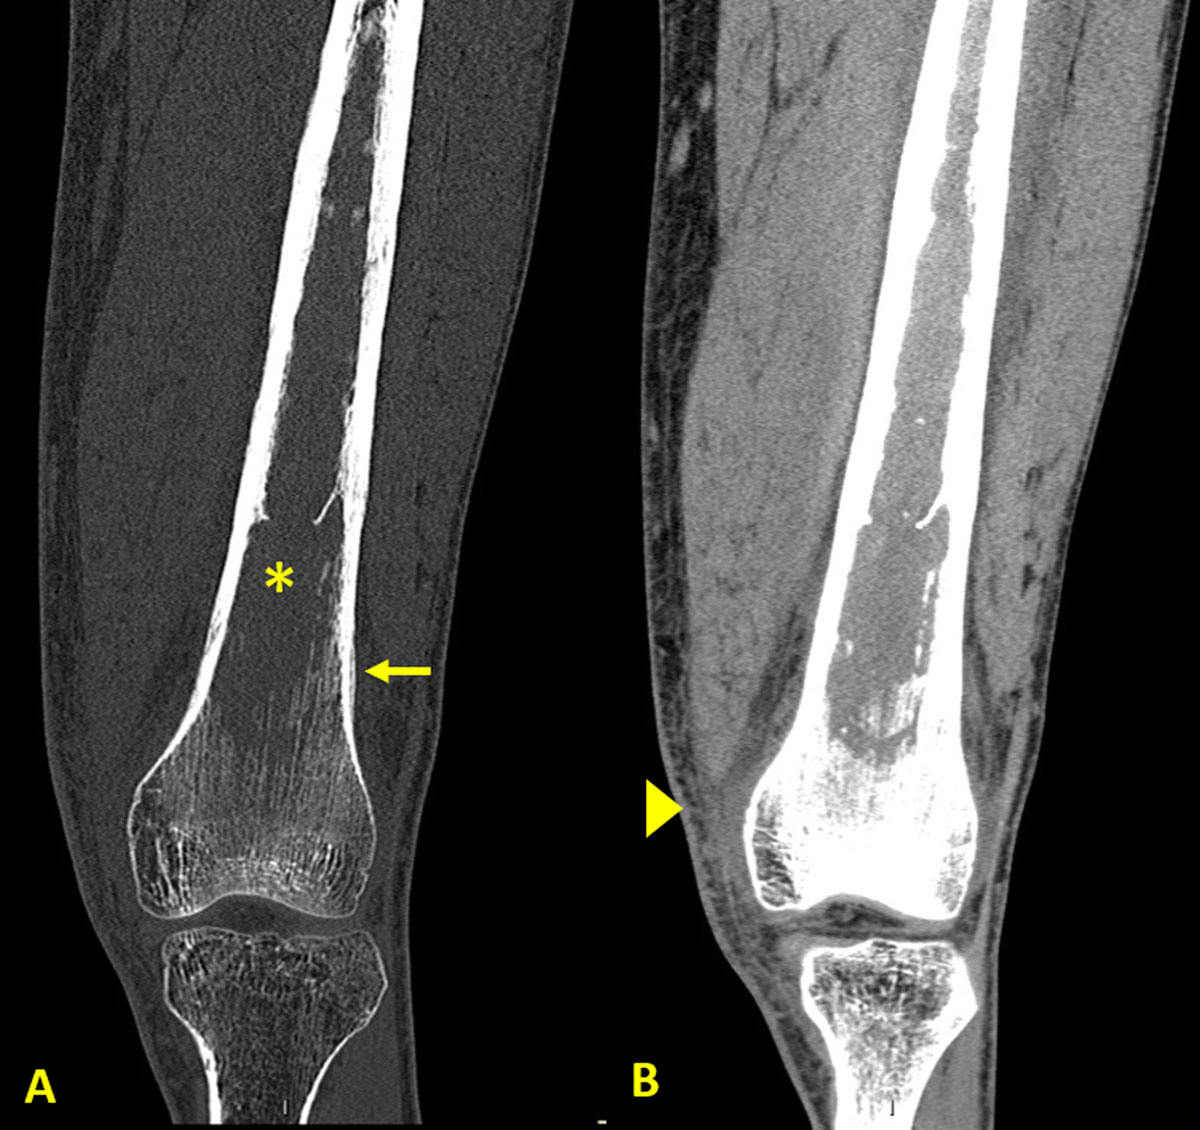

The patient underwent a knee radiograph that showed a lytic bone lesion in the femur (asterisk in Figure 1) with lamellated periosteal reaction (arrows in Figure 1). Computed tomography (CT) of the knee showed loss of the normal trabeculation of the femur’s medulla (asterisk in Figure 2A), with preserved integrity of the cortex. Periosteal reaction (arrow in Figure 2A) and densification of the adjacent soft tissues (arrowhead in Figure 2B) were noticed.

Figure 2

CT of the knee showing preserved integrity of the femur’s cortex.